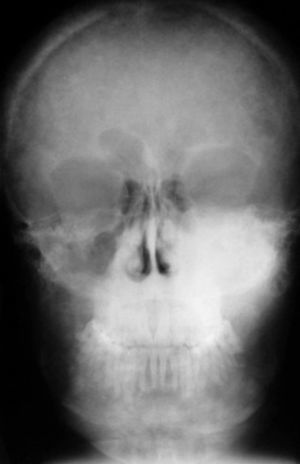

Caso clínicoPaciente, sexo masculino, 29 años de edad, derivado el año 2004 desde endocrinología al servicio de cirugía maxilofacial con diagnóstico de tumor maxilar en estudio. Sus antecedentes mórbidos incluyen insuficiencia renal crónica diagnosticada a los 18 años, en tratamiento con hemodiálisis 3 veces por semana. A los 27 años se detecta, en una ecotomografía doppler, la presencia de nódulos bilaterales compatibles con adenoma paratiroideo y niveles de PTH de 2.448pg/ml (150-500pg/ml). Con estos antecedentes se diagnosticó hiperparatiroidismo secundario. Se realiza la paratiroidectomía parcial y se indica tratamiento farmacológico protocolario, obteniéndose la normalización de los niveles séricos de calcio, pero manteniéndose altos los niveles de paratohormona. El paciente nota aumento de volumen en la zona maxilar izquierda, de crecimiento lento pero progresivo con 2 años de evolución, desde el año 2002. Al momento de consultar en nuestro servicio, clínicamente se observa aumento de volumen que compromete el maxilar superior izquierdo en su cara anterior, posterior y paladar duro, de consistencia firme, de 4cm de diámetro, indoloro, cubierto por piel y mucosa de aspecto normal, sin alteración sensitiva, que produce asimetría y deformación facial evidente (figs. 1 y 2). En los exámenes radiográficos se observan múltiples imágenes osteolíticas que afectan el cráneo, la mandíbula y el maxilar izquierdo (figs. 3 y 4). El TAC muestra tumoración exofítica que compromete maxilar izquierdo, seno maxilar, fosas nasales y piso de la órbita izquierda (fig. 5).